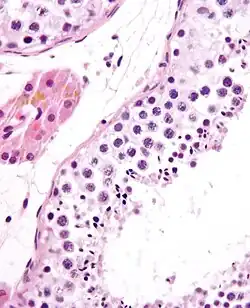

Normal spermatogenesis, testis biopsy.

High-power view of a seminiferous tubule with normal spermatogenesis.